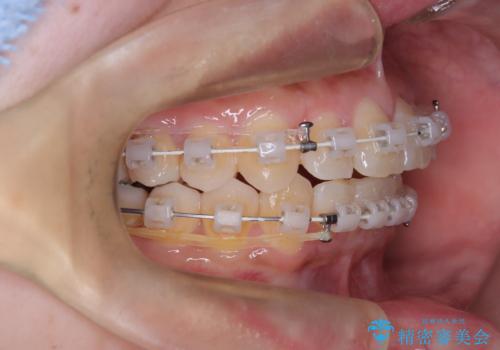

非抜歯で整える前歯の矯正

- 矯正装置

- 審美ワイヤー

- 患者様は、前歯の重なり(叢生)が気になるとのことでご来院されました。診断の結果、奥歯を後方に移動することで前歯にスペースを確保し、非抜歯で歯列を整える方針としました。治療には審美性の高いホワイトワイヤーを使用し、奥歯の遠心移動にはリンガルアーチを装着しました。治療期間は約2年を予定し、月に一度の調整を通じて歯の動きを細かく管理しました。

非抜歯矯正は、歯を抜かずに自然な歯列を作るため、歯列全体のバランスを考慮する必要があります。本症例では、リンガルアーチによる奥歯の遠心移動を用いましたが、初期段階で軽い違和感を覚える方もいらっしゃいます。そのため、装置装着後のケアや食生活について詳しく説明を行い、患者様にも協力いただきました。また、審美ワイヤーを使用することで、日常生活での見た目のストレスを軽減し、治療を快適に進めることができました。